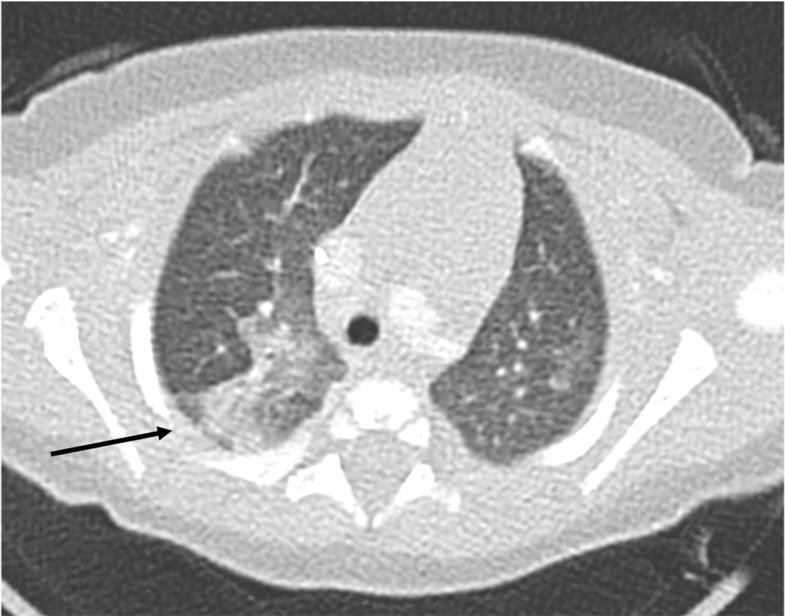

Early: "Halo" sign

Imaging of Covid 19 infection in children

Local infection Surr vasc congestion